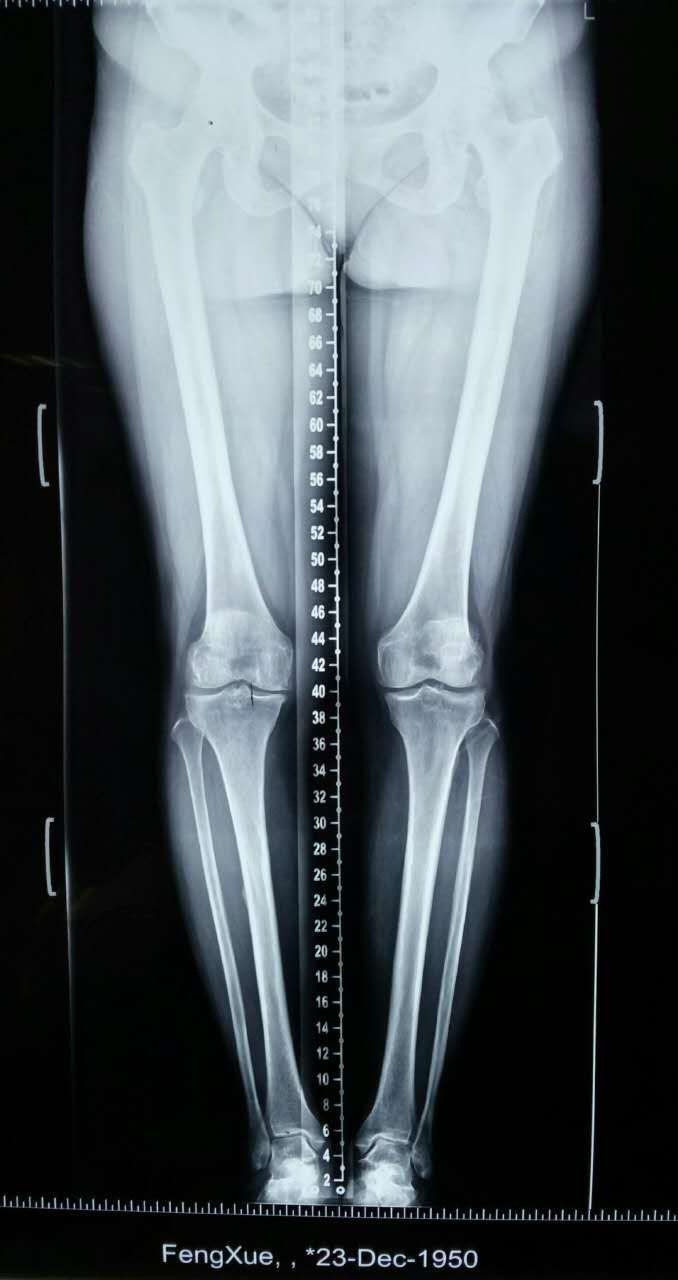

老年人膝关节增生疼痛,o形腿能治好吗?

图片尺寸1200x1600